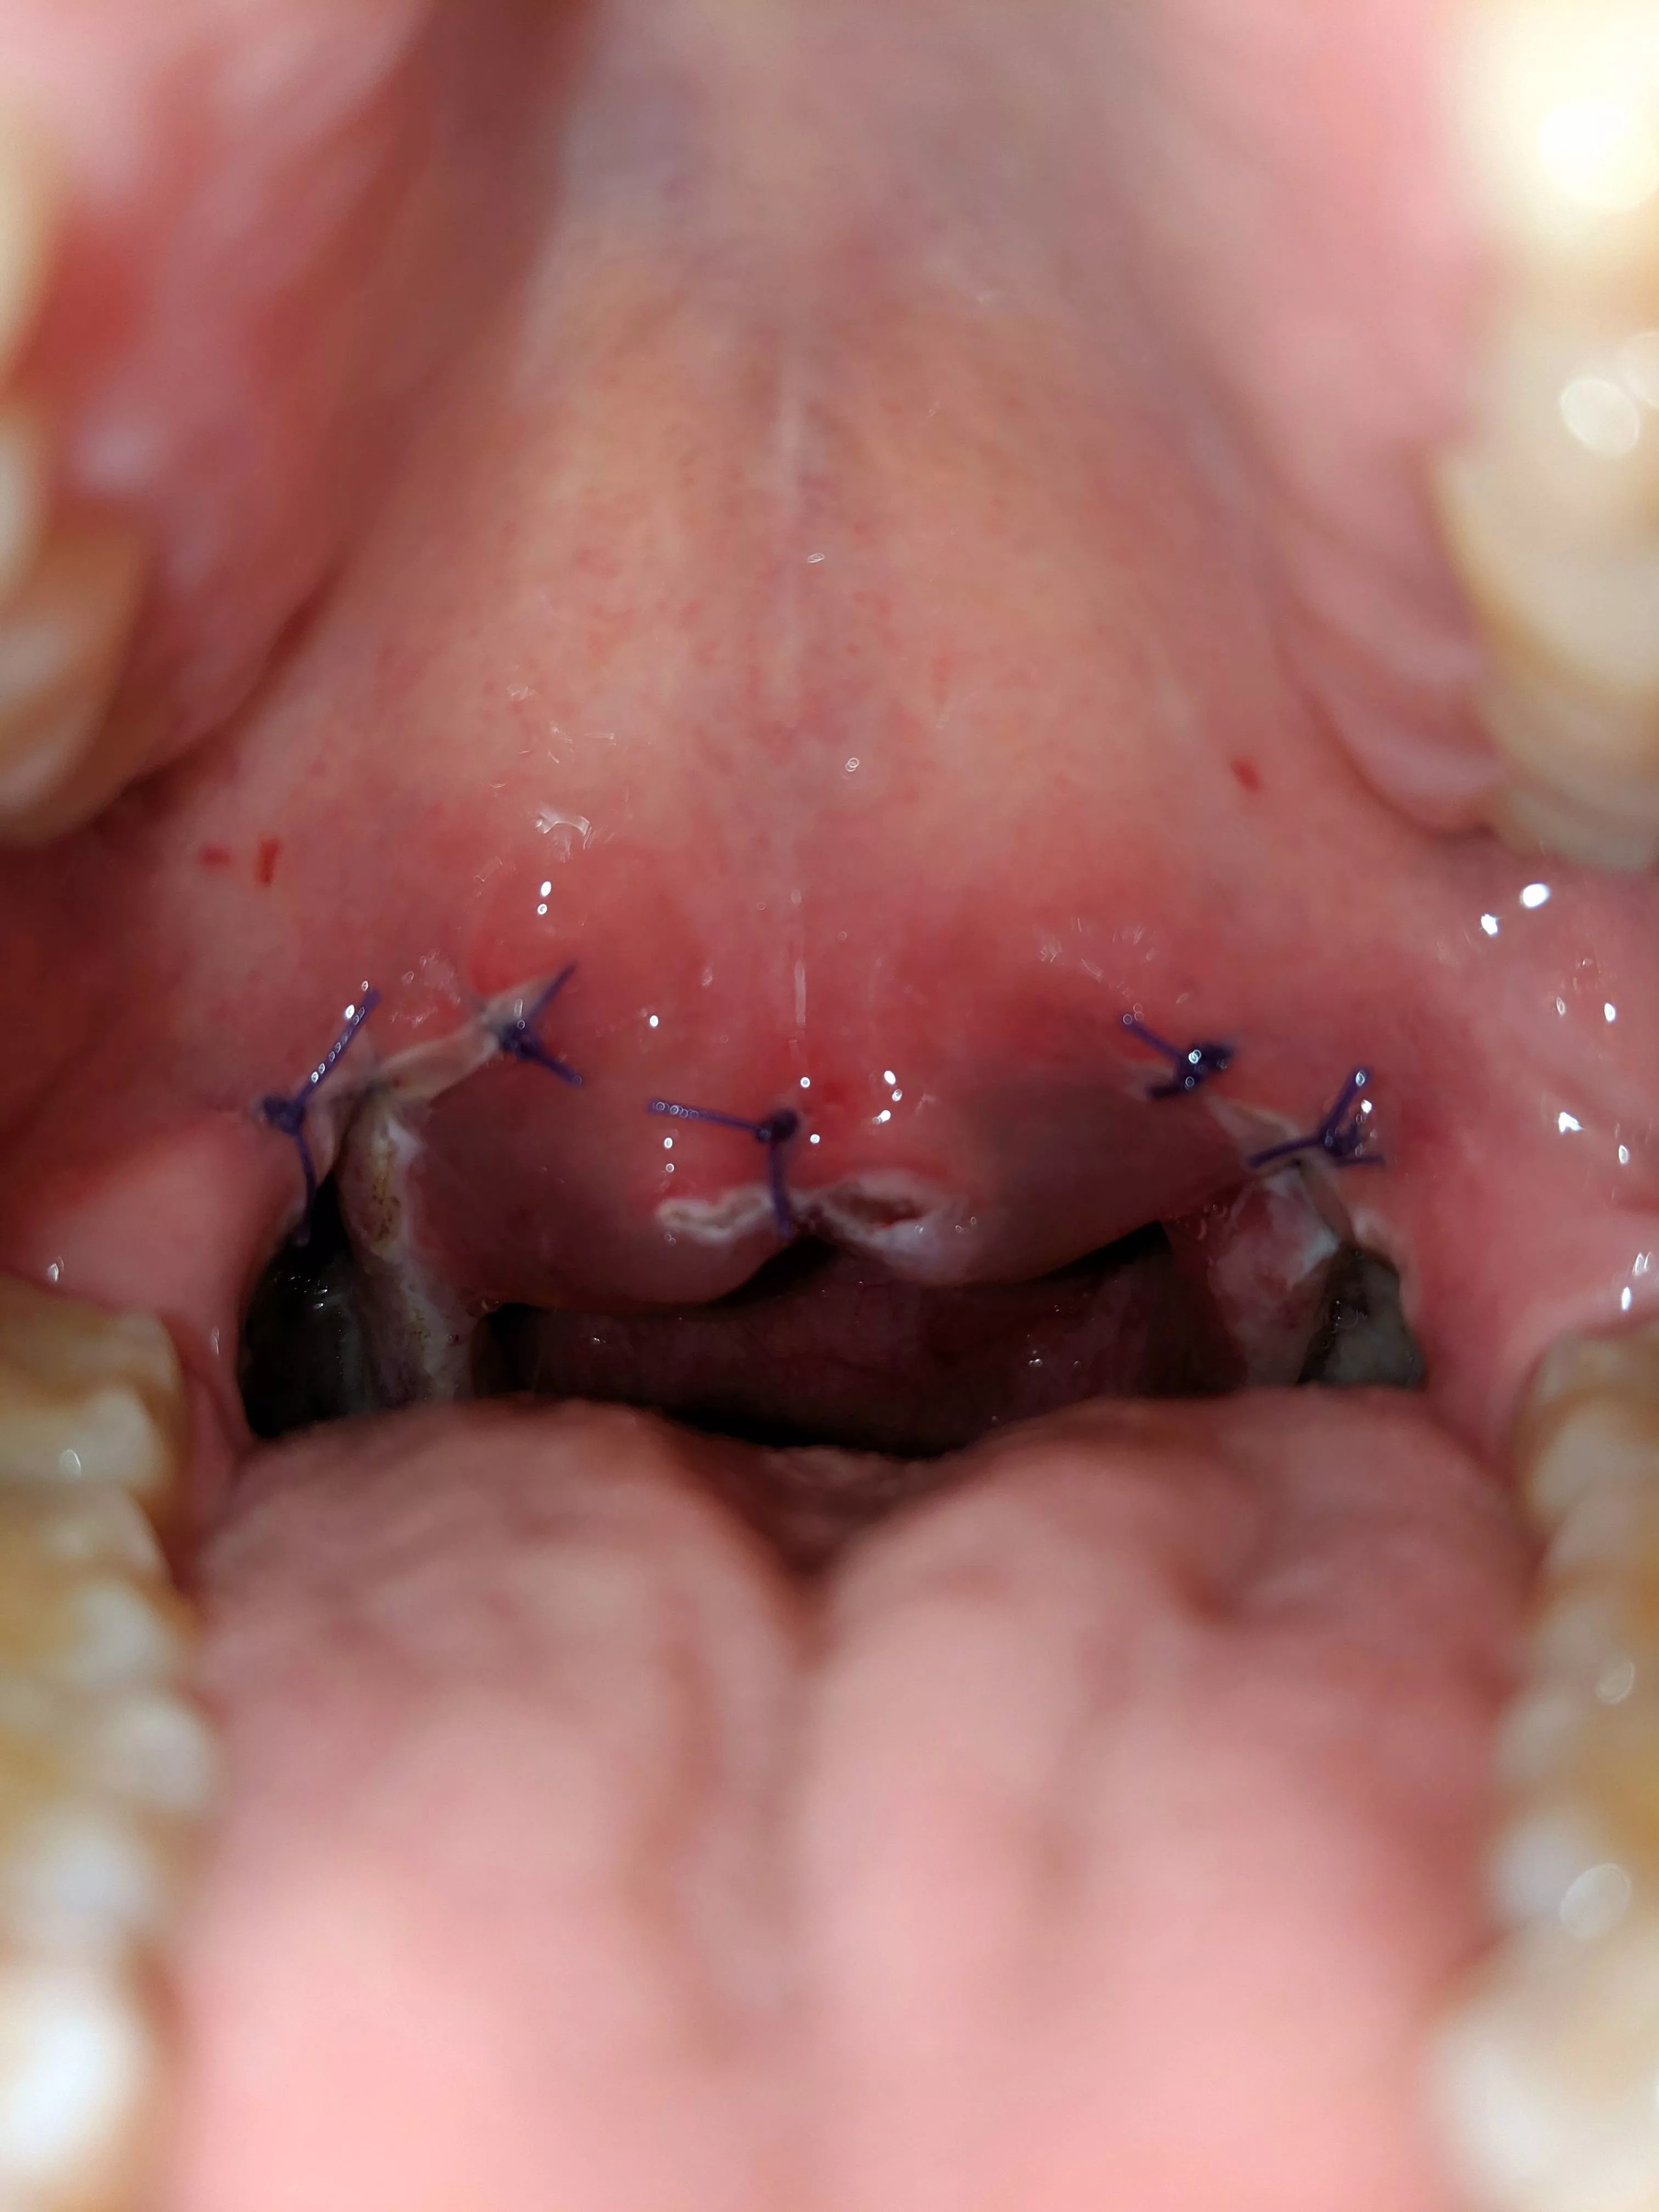

No pop but out of interest to you all on the subject of tonsillectomy